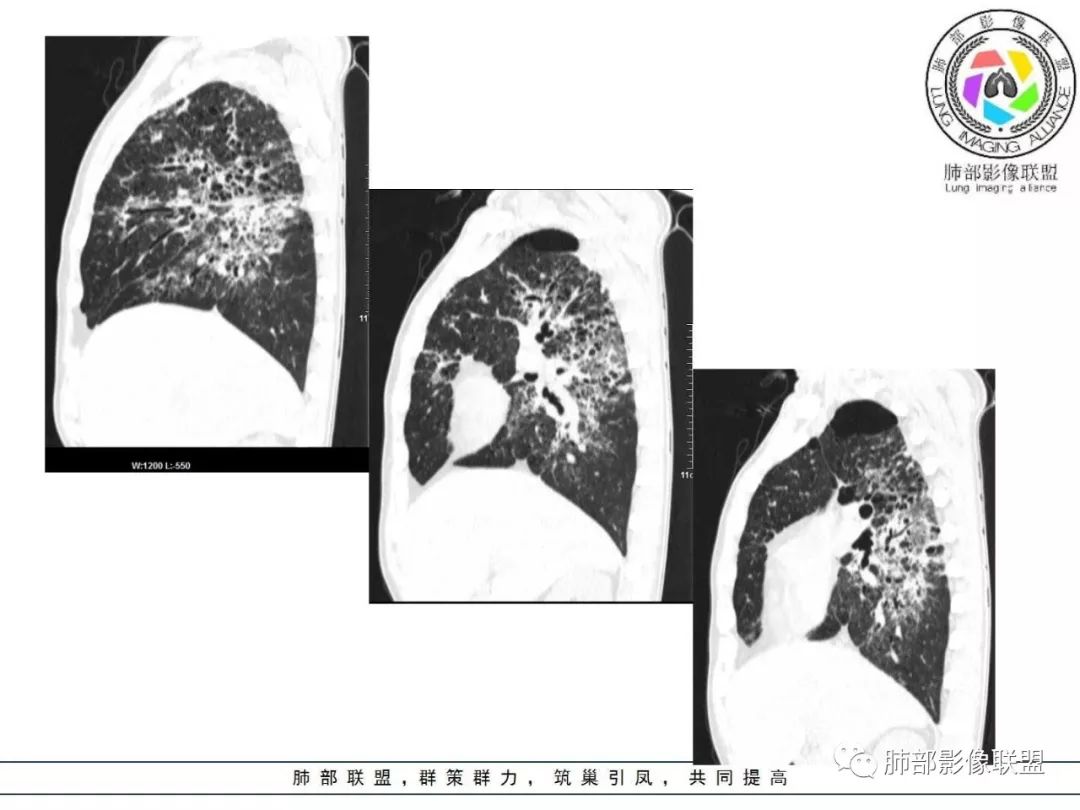

双肺间质性病变,中央间质增厚,胸膜下间质增厚,左侧胸膜肥厚,胸廓变小,肋间隙变窄。

胸部CT:两肺弥漫病灶,磨玻璃影,少许实变,部分累及胸膜,磨玻璃区可见囊?少许胸腔积液,两肺可见结节,支气管血管束增粗,小叶间隔增厚,支气管走形有扭曲扩张,可见纤维化。气肿、大泡。考虑:感染性病变,PCP?查下HIV,CD4,G等。鉴别结核、结缔组织病肺浸润。

患者中年男性,发热1月,体温38℃-39℃,峰值40℃,无畏寒、寒战,伴黄痰,CRP升高明显,降钙素原稍升高,血沉、血糖正常。胸部CT:两肺弥漫病变,磨玻璃影+点片渗出,部分累及胸膜,磨玻璃区边界清楚,少许胸腔积液,两肺支气管血管束增粗,小叶间隔增厚,部分支气管走形有扭曲扩张,可见肺气肿、右肺尖肺大泡及部分纤维化改变。综合考虑:感染性病变。结核或PCP可能性大,鉴别风湿免疫、结缔组织疾病肺浸润和腺癌等恶性病变。

胸部CT:两肺弥漫病灶,中央间质分布为主,部分位于胸膜及叶间裂旁,磨玻璃影,斑片影,部分实性结节,肺气囊,支气管血管束增粗,小叶间隔增厚,叶间裂不均匀增厚,支气管走形有扭曲扩张,可见纤维化、气肿、大泡。考虑:LIP加MALT。鉴别PLCH、PCP、结核、结缔组织病肺浸润。

两肺弥漫病灶,中央间质分布为主,部分位于胸膜及叶间裂旁,磨玻璃影,斑片影,部分实性结节,肺气囊,支气管血管束增粗,小叶间隔增厚,叶间裂不均匀增厚。考虑:间质性肺病,LIP,鉴别OP

病灶呈片状磨玻璃密度影,呈典型的烟花征。磨玻璃影密度偏高,有网结节样改变,与正常肺实质分界清楚,且常见相对高密度的勾画。

烟花征分为3肿类型:晕征、反晕征及均匀分布。

病变一般沿血管支气管束分布或小叶分布,一般上肺多于下肺(这与常见继发性肺结核分布相若)。

常会伴有其他继发性肺结核病灶,如斑片影、结节影,树芽征,新旧不等改变。

2. 肺气肿背景(小叶中心性肺气肿);双肺多发病灶整体沿血管支气管束及胸膜下分布,以上叶及下叶背段分布为主,有实变及GGO,边界清楚,有树芽,小叶间隔及中央间质增厚,叶间裂见到多发结节,部分支气管不规则牵拉扩张,提示病灶纤维化明显,结合临床病史,考虑病灶为间质性感染,肺门及纵隔内有钙化淋巴结,小叶间隔结节,考虑淋巴道增值性疾病可能,综合常规要怀疑间质性肺结核。